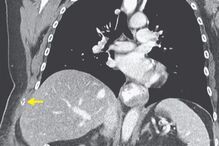

Uma mulher de 66 anos partiu a costela do lado direito após duas semanas intensas de tosse seca, resultantes de uma gripe que tinha contraído, em Massachussetts, nos EUA.

A utente, que tinha sido diagnostica com gripe uns dias antes, dirigiu-se ao hospital com muitas dores. Foi aí que o médico se apercebeu que tinha um enorme hematoma por baixo do peito direito e uma dor aguda sempre que se lhe tocava.

Um exame revelou que a norte-americana tinha uma fratura nas costelas e ainda uma hérnia na parede do tórax.

A equipa médica acredita que a fratura terá sido causada pela tosse forte que a mulher sofreu nos últimos dias. A norte-americana de 66 anos acabou por ser operada e foi recomendada a tomar um antibiótico mais forte para curar a gripe e a tosse.